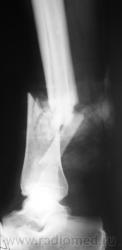

Наверное, открытый?

Нет. Закрытый.

Здравствуйте, уважаемый Валентин Львович! Очень похож на "бамперный перелом". У меня вопрос - а почему снимки без шины? Ведь пациенту наверняка было больно при проведении исследования в двух проекциях.

Вопрос, по поводу шины правильный, который в "нормальных" ЛПУ не подлежит обсуждению. У нас, такая транспортировка считается обычной...

Чегото на боковом структура кости не странная? Как будто в области перелома есть еще дополнительное тенеобразование..     Мягкие ткани?

Виктор.